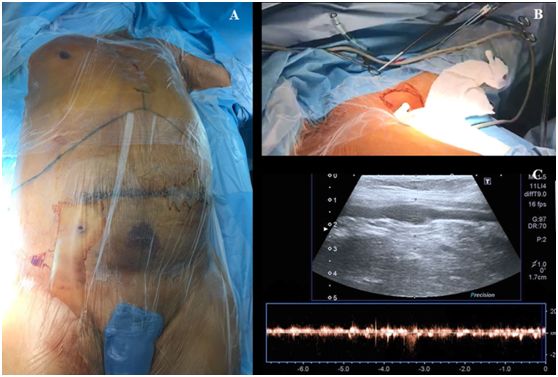

操作前,将患者置于平躺仰卧位,头部自然居中位,左上肢掌心向上外展90度(图1,A)。超声探头上涂上耦合剂,用无菌保护套包裹超声探头及导线。

从上臂近端至腋窝处超声预扫描,同时探查腋动脉和腋静脉的长轴平面(图1,BC),注意用最小的压力来控制超声探头,避免把血管压瘪。然后用多普勒和/或彩色血流来评估静脉及动脉的通畅性。

图1,A肝移植术患者体位,B-C腋静脉超声预扫描。